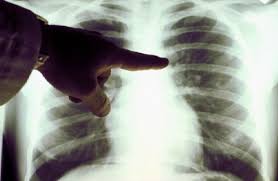

Диагностика при кальцинозе основывается на рентгенологическом исследовании. Соли кальция являются рентгенпозитивными, поэтому их скопления в легком видны как затемнения неправильной формы. Во время исследования врач должен обратить внимание на следующие факторы:

1. Сколько образований есть у пациента (единичные кальцинаты или множественные);

2. Какого они размера (мелкие кальцинаты или крупные);

3. В каких областях органа они расположены (в верхних, нижних долях или кальцинаты в корнях легких).

Это необходимо для того, чтобы оценить общее состояние пациента и сделать прогноз течения его заболевания. Кроме того, особенности расположения очагов также являются диагностическим признаком. Так, при туберкулезе патологические очаги в основном затрагивают область верхних долей органа, пневмония чаще всего развивается в нижних долях, а единичный абсцесс может поражать корень легкого.

Подтвердить наличие кальцинатов поможет более точное рентгенологическое исследование – компьютерная томография. Ее возможности позволяют не только обнаружить кальциевые камни, но и установить их точное расположение. Благодаря высокой разрешающей способности и послойной визуализации ткани органа КТ позволяет выявить множественные кальцинаты, некоторые из которых не заметны на обычной рентгенографии.